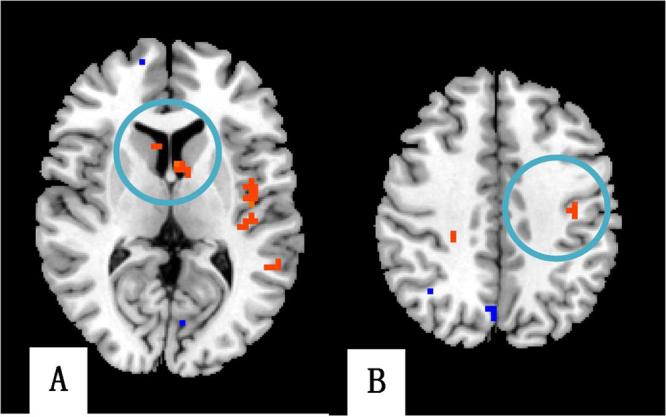

Research on the mechanism of post stroke depression (PSD) is the key way to improve the treatment of PSD. However, the functional brain network of PSD has not been entirely supported by the results of functional magnetic resonance imaging (fMRI) studies. The aims of this study are to investigate the brain response of PSD in three different lesions. The brain responses of the three PSD subgroups were similar. However, each subgroup had its own characteristics of the brain network. In the temporal lobe subgroup, the right thalamus had increased degree centrality (DC) values which were different from the other two subgroups. In the frontal lobe subgroup, the left dorsolateral prefrontal cortex, caudate, and postcentral gyrus had increased DC values which were different from the other two subgroups. The hemodynamic response of PSD indicates that PSD has activities of similar emotional networks, of which the negative network realizes its function through the limbic system and default mode network. The brain network has unique characteristics for different lesion locations. The neurological function of the lesion location, the compensatory mechanism of the brain, and the mechanism of integrity and locality of the brain are the important factors in the individual emotional network.

研究脑卒中后抑郁(PSD)的发病机制是提高 PSD 治疗效果的关键途径。然而,功能磁共振成像(fMRI)研究结果并未完全支持 PSD 的功能脑网络。本研究旨在探讨三种不同病变部位 PSD 的脑反应。三组 PSD 亚组的脑反应相似,但每个亚组的脑网络都有其自身的特点。在颞叶亚组中,右侧丘脑的度中心度(DC)值增加,与其他两组不同。在额叶亚组中,左侧背外侧前额叶皮层、尾状核和中央后回的 DC 值增加,与其他两组不同。PSD 的血液动力学反应表明 PSD 具有相似的情绪网络活动,其中负性网络通过边缘系统和默认模式网络实现其功能。不同病变部位的脑网络具有独特的特征。病变部位的神经功能、大脑的代偿机制以及大脑的完整性和局部性机制是个体情绪网络的重要因素。